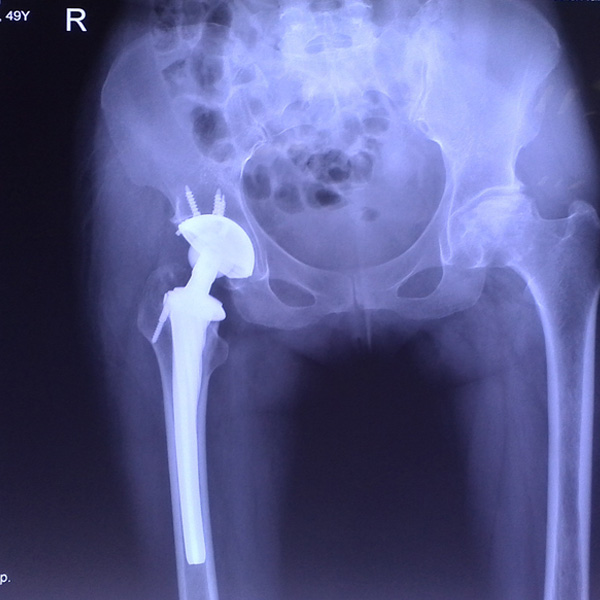

• 先天性髖關節脫位先天性髖關節脫位手術后手術前

先天性髖關節脫位

患者王某某,女,41歲,從會走路以來就發現一條腿長,一條腿短,也就是人們俗稱的“跛子”,之前雖然兩條腿長短不一,但起碼還可以走路,維......